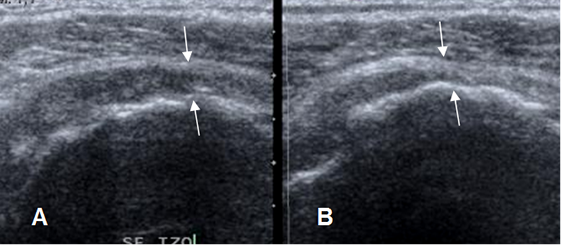

Fig 105. Irregularidad en la cortical.

A: Rx AP y B: Ecografía coronal. Irregularidad en el borde superior de la cabeza humeral, que se traduce en la ecografía, como imágenes ecogénicas. (Flechas delgadas). El tendón del supraespinoso ha perdido su convexidad superior, por ruptura parcial. (Flecha gruesa).

Fig 106. Pérdida de la convexidad del tendón.

Ecografía coronal. Pérdida de la concavidad superior del tendón supraespinoso, por ruptura parcial. (Flecha delgada). Normalmente el reborde del tendón es paralelo, a la cabeza del húmero. (Flecha gruesa).